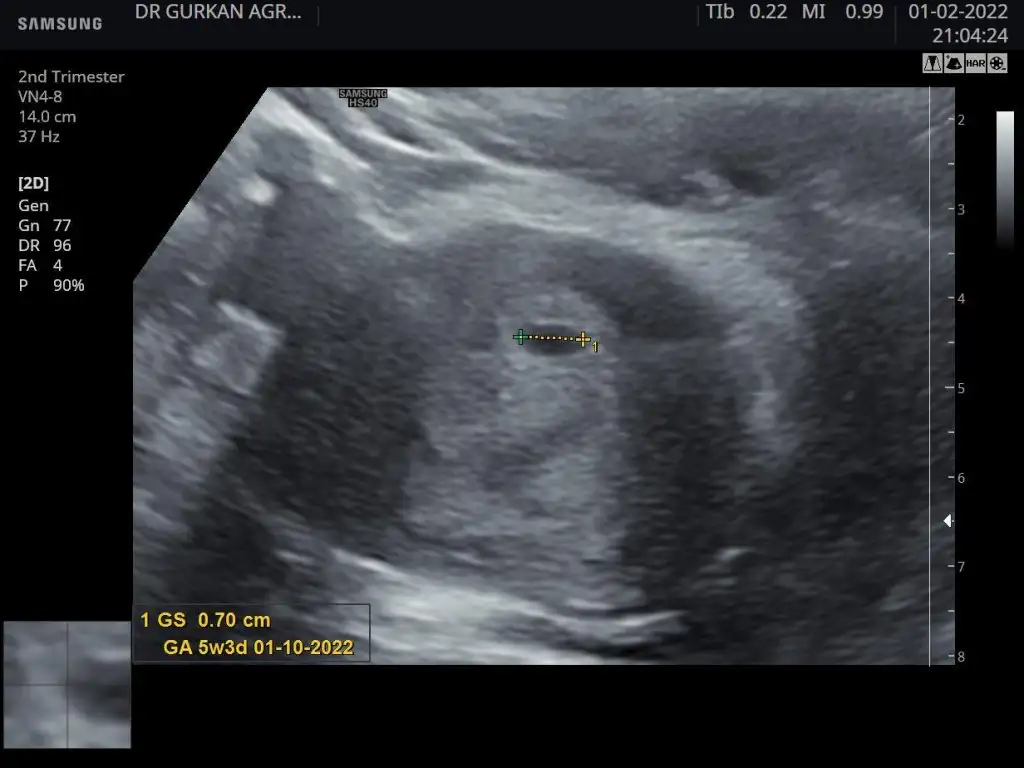

Ikra meyra Ikra meyra merhabalar bize de tahmin yürütür müsünüz ? 3 adet foto var 1. 4 haftalık

2. 6 haftalık

3. 9 haftalık

Kızlar sizceeeeee